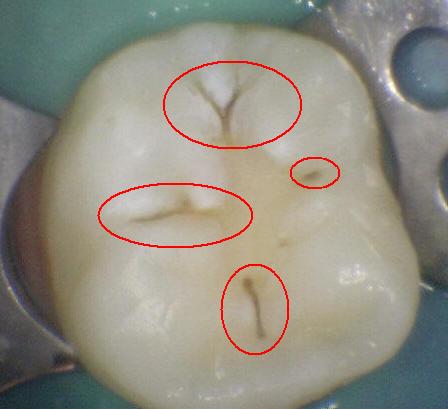

Código 3

(Caries Moderada): Ruptura

localizada del esmalte debido a caries sin dentina visible.

-

Cavidad en el margen de la

restauración/sellante menor a 0,5mm, además de tener una

opacidad o una pigmentación relacionada con

desmineralización que no es compatible con la apariencia

clínica de esmalte sano o con una sombra subyacente en

la dentina.

Utilizar una

sonda con

presión suave. para identificar la pérdida de

anatómica.

Opacidad o decoloración consistente con

desmineralización.